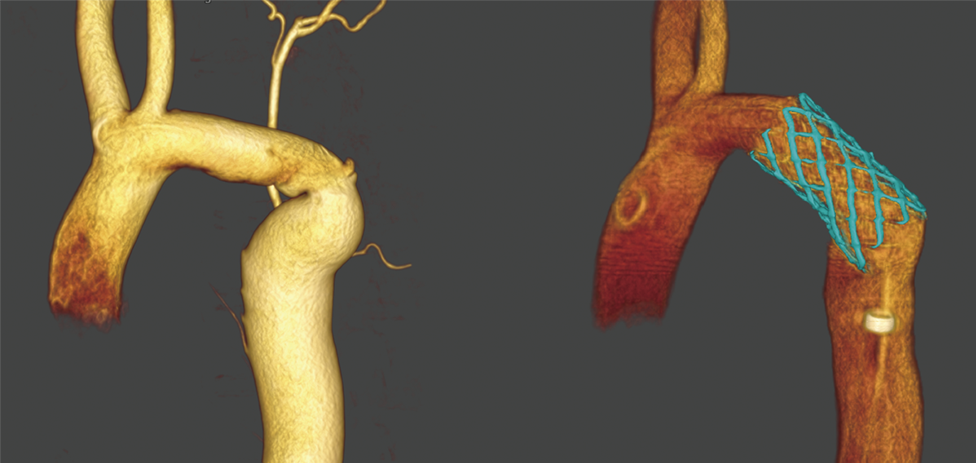

3D DA (Alpha CT Vessel)

Обертання С-дуги у комбінації із високою швидкістю «зйомки» може використовуватися для створення 3D реконструйованих об’ємів анатомії судин. Отриманий 3D-об’єм судин можна обертати в будь-якому напрямку, щоб надати клініцистам додатковий огляд анатомії, та допомогти їм у діагностиці та лікуванні під час інтервенційних процедур. Огляд зображень, отриманих за допомогою 3D-ротаційної візуалізації, дозволяють лікарям візуалізувати різну анатомію судин, таку як ділянки стенозу, відрив аномальної судини, судину, що живить АВМ, та інші патології зі всіх ракурсів.

Лікарі можуть використовувати цю об’ємну візуалізацію судин під час маніпулювання катетером чи іншим пристроєм у судині.

Техніка Device Fusion до і після встановлення стента